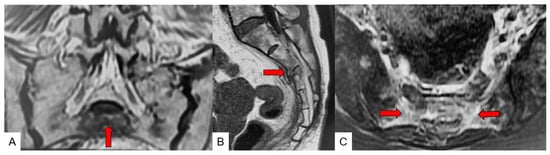

3.4. Typical SIF Case